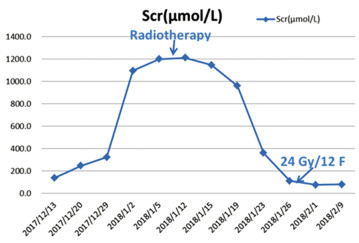

2017年12月20日患者血清肌酐开始升高,随后病情迅速进展,并发肾积水、梗阻性肾功能衰竭及尿路感染,通过输血、抗感染及血液透析治疗后缓解。考虑到生活质量,患者拒绝膀胱根治性手术切除。2018年1月9日开始实施放射治疗。放疗计划:GTV1(瘤床):64 Gy/32 Fr,CTV1(膀胱外放2 cm):54 Gy/27 Fr,CTV2(淋巴结引流区):50 Gy/25 Fr。当照射剂量达到24 Gy/12 Fr时,患者的血清肌酐恢复正常。血清肌酐(Scr)的变化趋势见图 3。患者在2018年2月21日结束放疗,此时腹部MRI检查提示膀胱内仍有残留肿瘤。2018年3月9日开始行吉西他滨+洛铂(吉西他滨1.7 g,d1、8+洛铂50 mg)化疗一个疗程,此后患者因化疗后骨髓抑制终止化疗。考虑仍有肿瘤残留,建议重启化疗,但患者拒绝化疗,患者自行口服两个疗程阿帕替尼。2018年6月8日复查盆腔磁共振提示肿瘤仍有部分残留,于2018年7月9日、2018年8月3日、2018年8月24日、2018年9月24日、2018年10月15日和2018年11月28日给予吉西他滨(1.6 g,d1、8)治疗六个疗程。治疗结束后患者残留病灶基本消退。此后患者3个月规律复查一次。由于患者治疗后无尿路症状不适,因此患者拒绝膀胱镜检查,只接受无创的腹部CT增强及尿脱落细胞学检查。最近一次于2022年12月13日复查腹部增强CT及尿脱落细胞学检查,提示未见肿瘤复发及转移,见图 4。随访至今患者无病生存期超过5年。